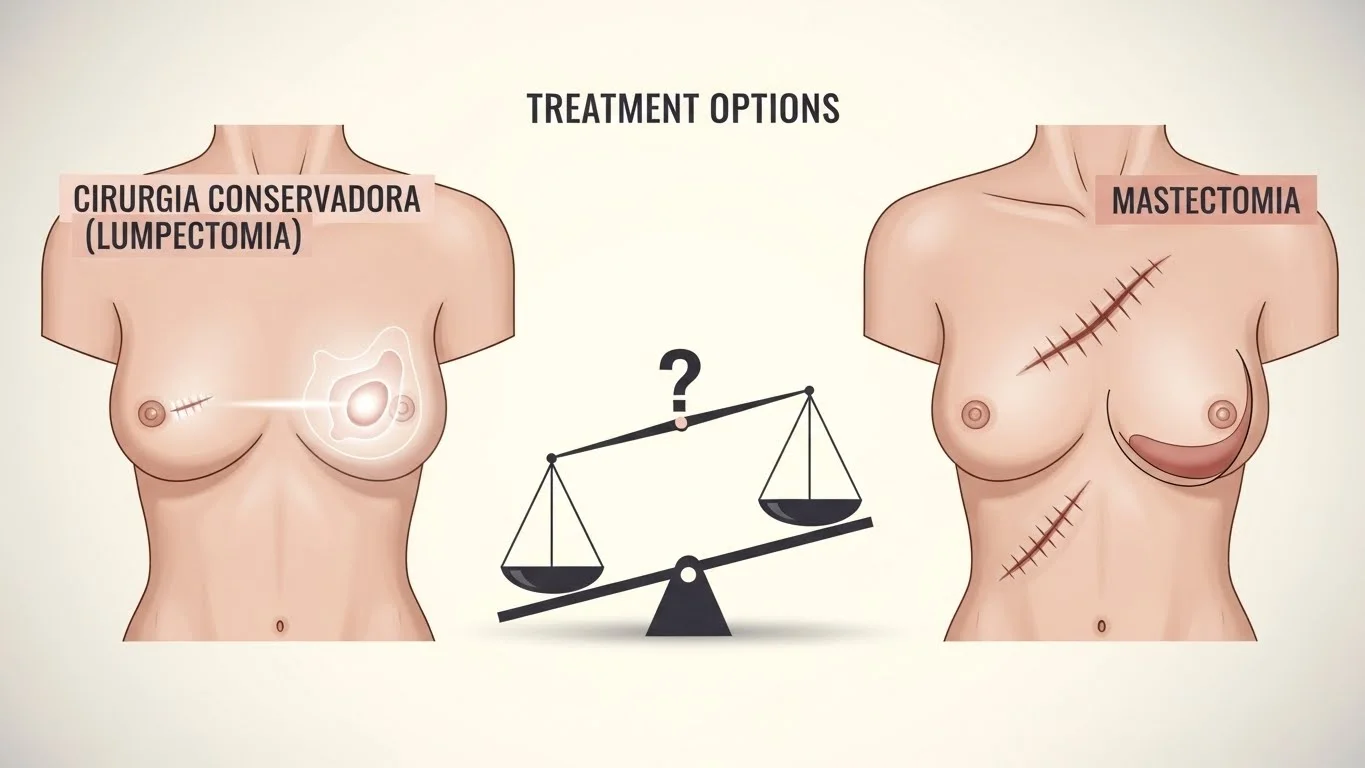

Cirurgia Conservadora da Mama vs Mastectomia: quais são as opções de tratamento Quando falamos em cirurgia para câncer de mama,...